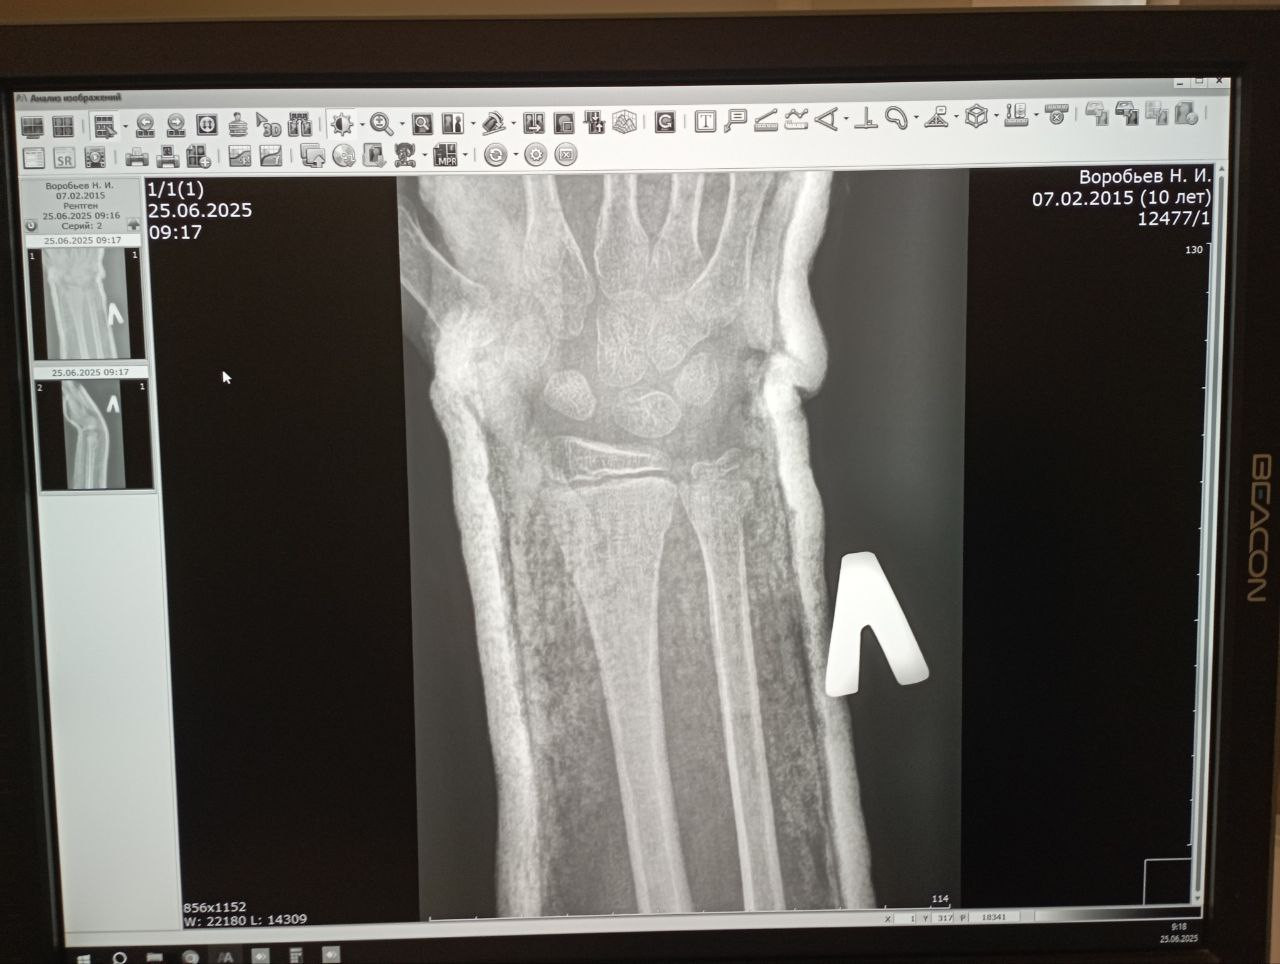

Здравствуйте По снимкам виден перелом дистального метаэпифиза лучевой кости (вероятно с типичным смещением у детей) с наложением гипса. Это частая травма в детском возрасте. Обычно при таких переломах гипс носят:

Сегодня был 7 день после травмы. Мы сделали снимок, можете просмотреть пожалуйста и прокомментировать. Спасибо

По новым снимкам видно, что положение костных отломков остаётся удовлетворительным, вторичного смещения нет. Контур перелома прослеживается, начальных признаков костной мозоли пока не видно (что нормально на 7 сутки). Гипс можно сохранять дальше, как минимум до 3-4 недель от момента травмы. Если самочувствие хорошее то лечение продолжается по плану.